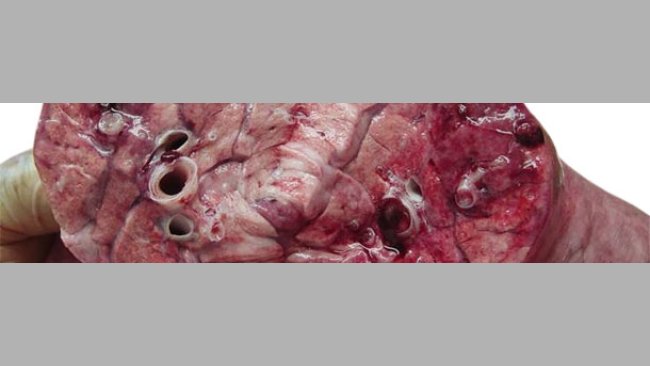

Caso clínico: Neumonía necrótica en lechones lactantes

En una granja de multiplicación situada en México se observa un aumento de la mortalidad en maternidad coincidiendo con un aumento de la temperatura y humedad ambientales.